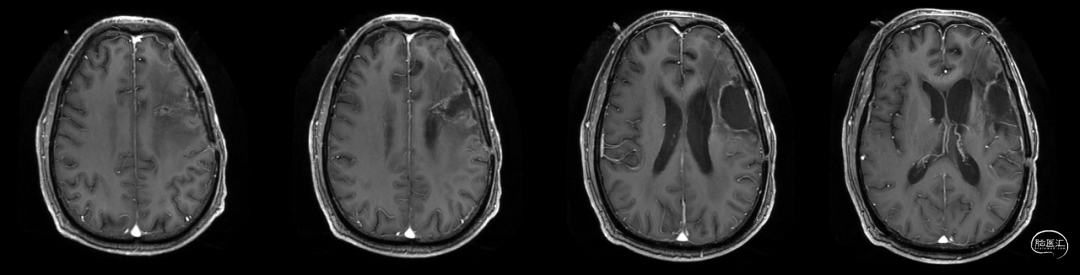

肿瘤电场治疗16天,RT后1月(2020-07-22):图示。

放疗后8月(2021-03-17):如视频和图像。

术后5周开始实施标准的新STUPP方案的辅助治疗,即在同步放化疗后,辅助替莫唑胺化疗的同时使用了电场治疗。目前生存25月,且临床和影像学表现均提示稳定,未见复发迹象。期间,在放疗后7月时复查MRI提示异常FLAIR信号区增大,经我院MDT讨论,考虑到强化信号减轻,无明显占位效应,患者无症状体征,考虑是治疗后水肿,非进展,故继续按原方案治疗。放疗后17月复查MRI出现术区边缘局部强化范围稍增大,但PWI示强化区局部呈低灌注且未见弥散受限表现,MDT讨论考虑为假性进展,继续原方案治疗。后续复查MRI强化范围减轻,证实了MDT的判断证实疾病稳定。患者生存时间已达25个月。全程安全顺利,仅出现一过性轻度皮肤反应。

辅助TMZ治疗过程中每2-3月复查MRI。治疗中曾出现水肿范围增大,尽管有部分区域弥散受限和MRS异常及血流量增加,但是临床症状未加重,仍继续原方案治疗,后续监测PWI显示病变区灌注减低。提示持续肿瘤电场治疗可以使病变长期稳定。此患者每天佩戴肿瘤电场治疗时间接近22小时,中间出现头皮发红和小水泡,经局部外用皮质类固醇和外用抗生素,暂停2天治疗恢复。至今随访25月稳定。说明肿瘤电场治疗联合TMZ治疗较单TMZ治疗明显延长胶质母细胞瘤患者PFS及OS,临床应积极推广使用。